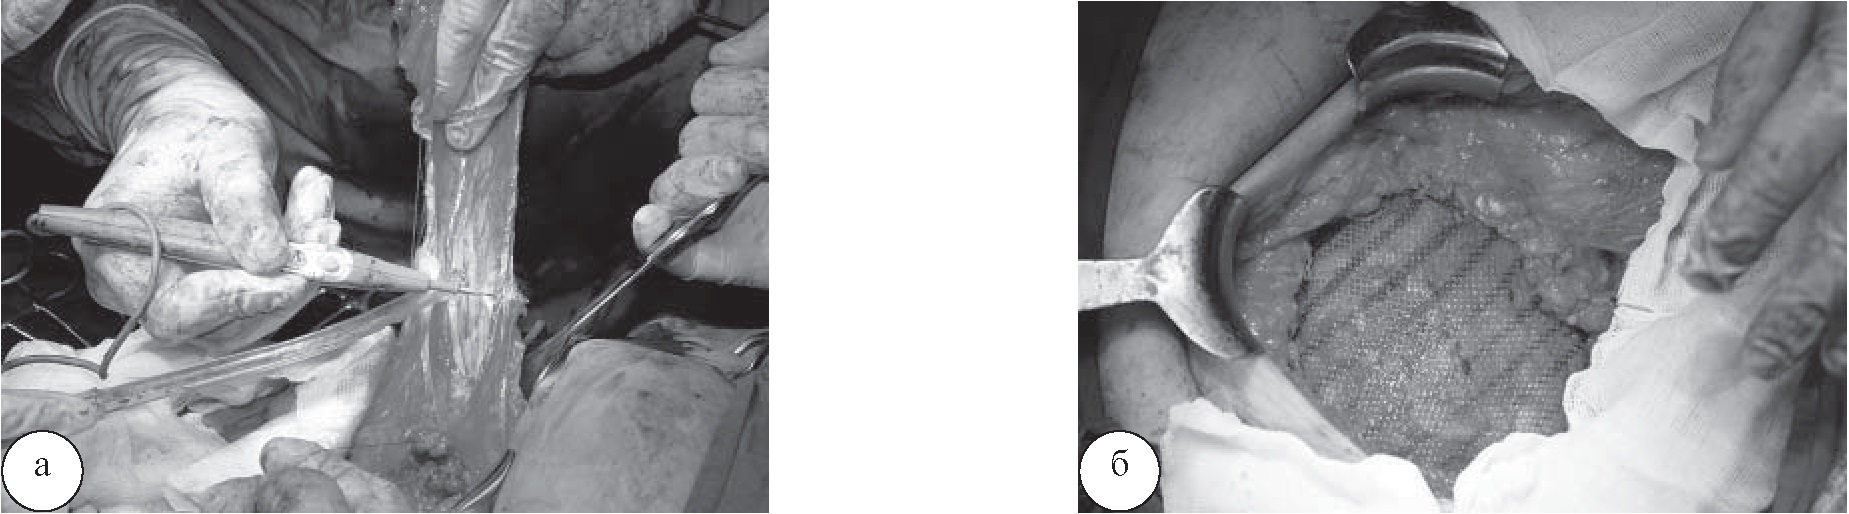

Грыжевой мешок иссечен, брюшина ушита непрерывным швом. Выполнена пластика грыжевых ворот по Лихтенштейну (рис. 3).

Рис. 3. Иссечение грыжевого мешка (а); пластика грыжевых ворот сетчатым эксплантатом (б)